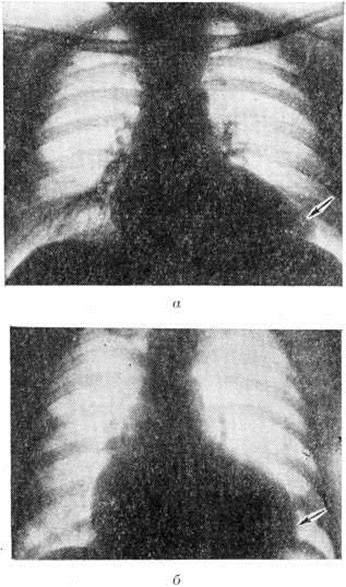

Миокардит Абрамова — Фидлера по своей клинические, картине практически неотличим от идиопатической застойной кардиомиопатии (смотри полный свод знаний), а нередко и от идиопатической гипертрофии миокарда, в частности от субаортального стеноза. В пользу Миокардит говорит связь начала или обострения заболевания с инфекцией (чаще вирусной), приёмом лекарственных средств и другими аллергизирующими факторами. Наличие признаков воспаления и аллергии, особенно обнаружение в крови антител к миокарду, делают диагноз миокардита Абрамова — Фидлера более достоверным, хотя отсутствие их не исключает его возможности. Течение миокардита Абрамова — Фидлера более острое (недели, месяцы), кардиомиопатий — более затяжное (годы и даже десятилетия), хотя в результате разработки методов лечения появились подострые и хронический формы миокардита Абрамова — Фидлера. При дифференциальной диагностике с субаортальным стенозом ведущую роль играют данные рентгенологическое исследования (рисунок 10), особенно вентрикулографии, а также эхокардиографии (наличие асимметрической гипертрофии межжелудочковой перегородки). Миокардит Абрамова — Фидлера, в клинические, картине которого преобладает болевой синдром, нередко приходится дифференцировать с острым инфарктом миокарда при ишемической болезни сердца; вместе с тем боль при Миокардит может быть действительно связана с некрозом миокарда, характерным для этой формы.

Мерцательная тахиаритмия может в значительной степени затушевать характерную аускультативную картину порока сердца. Поэтому в дифференциальной диагностике приобретает большое значение анамнез (указания на ревматизм или порок сердца, даже предположительные, до развития сердечной недостаточности). Большое значение имеют рентгенологическое данные: для различных пороков характерны своеобразная конфигурация контуров сердца (выраженная сердечная недостаточность может в известной степени сгладить типичные рентгенологическое признаки порока). Клапанные поражения выявляются также с помощью эхокардиографии.